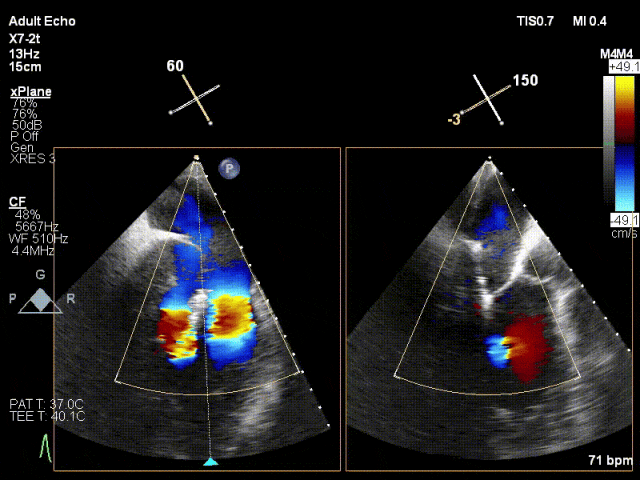

患者为41岁男性,心脏彩超提示:二尖瓣P2脱垂合并房性机制,左心扩大、瓣环扩张,反流主要来源于2区。反流宽度:20mm,2区瓣叶长度:2.2/1.3cm,AP径:43mm,瓣口面积:6.0cm²。

术前

X-plane 2区

X-plane 2区彩色

3D

3D彩色